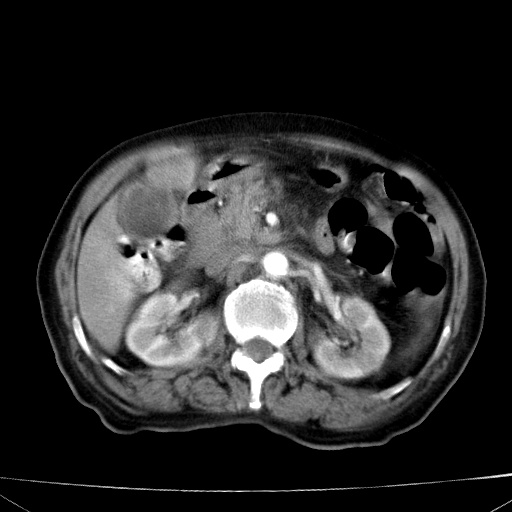

网站人气太旺!昨天的帖子就沉到海底,只好再发贴!ct18338:女 78岁,肝胆病变,已增强,再会诊!原帖链接:http://www.radida.com/bbs/forum.php?mod=viewthread&tid=50032

1)考虑胆囊癌侵犯肝脏并肝门区、腹膜后及右侧膈角后淋巴结转移。2)肝左叶近肝顶部囊肿。3)肝左叶肝内胆管结石。4)左肾近下极囊肿。

1、胆囊癌侵犯肝脏并腹腔及腹膜后淋巴结转移。

2、肝左叶外侧段囊肿。